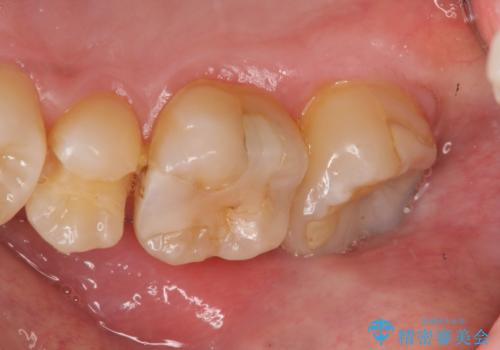

- 19万円(ゴールドインレー×2 セラミックインレー×1)費用は治療当時の料金となります

今回の治療では、虫歯を除去したのちより修復に適した素材を選択することで歯を削る量を可及的に少なくすることと、長期的な予後を期待できるような状態にすることができました。